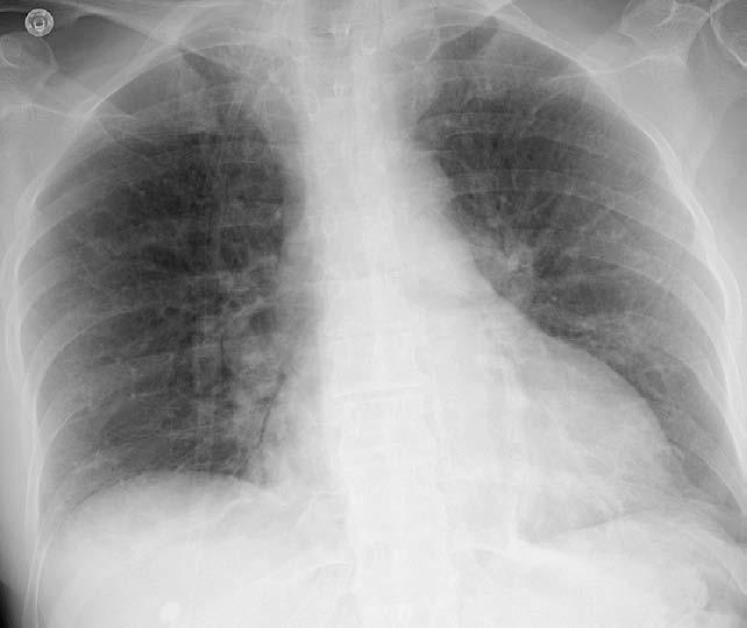

4.3 Image projections and additional characteristics

The mean and standard deviation images were obtained for visualization purposes. They were calculated from a random sample of 500 training examples.

These images showed relevant differences among the different x-ray projections (see Fig. 17). In PA, the mean shows that images were fairly aligned to the center, while the standard deviation for the same random sample of 500 images, in which higher values are whiter, indicates a higher variation at the boundaries when compared to the center. In AP supine position, the mean heart silhouette was enlarged. Vertical and horizontal lines in the pediatrics standard deviation illustrate that there are many sizes of frames enclosing the chest and part of the abdomen.

Refer to caption

(a) P-A

(b) Lateral

(c) AP supine

(d) AP erect

(e) Ribs

(f) Pediatric

(g) P-A

(h) Lateral

(i) AP supine

(j) AP erect

(k) Ribs

(l) Pediatric

Figure 17: From a) to f): Mean image by position view. From g) to l): Standard deviation image by position view.